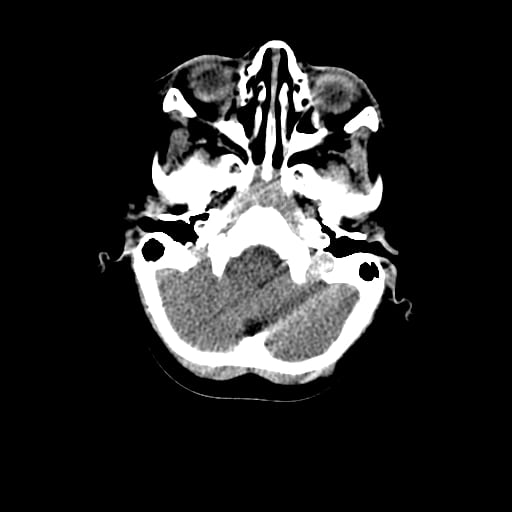

Age: 1

Sex: Male

Indication: Fall